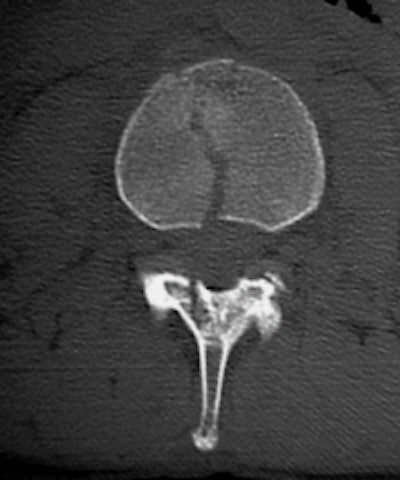

![]() ![]() |

The 0.5-mm slices offer fine bone detail, but pay a price on the soft-tissue images in terms of soft-tissue differentiation. Whereas the thicker (5-mm) slices fail to show the bone detail of the fracture well, but possess greater contrast resolution on the soft-tissue window to differentiate spinal cord from surrounding spinal fluid.